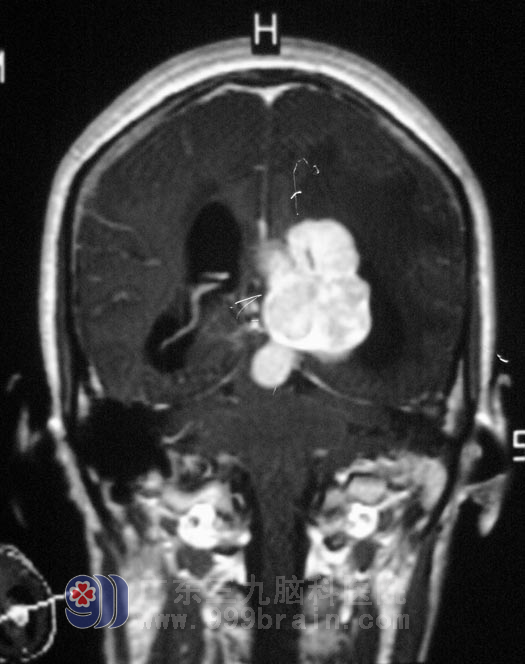

上图是一张40岁的吴女士手术前脑部影像资料,MR提示:左侧脑室内巨占位性病变,大小约47.8*31.9*44.5mm,增强明显。

广东三九脑科医院 综合神经外科 鲁明主任告知她及家人:脑膜瘤发生的病因可能与一定的内环境改变和基因变异有关,并非单一因素造成,可能与颅脑外伤、放射性、病毒感染以及合并双侧听神经瘤等因素有关。他们采纳了鲁明主任的建议,5月5日,吴女士在全麻下行左侧脑室内占位病变切除术,术中见肿瘤呈粉红色,边缘质硬,中心部位质软,血供丰富,呈花瓣状,在显微镜下全切除肿瘤: